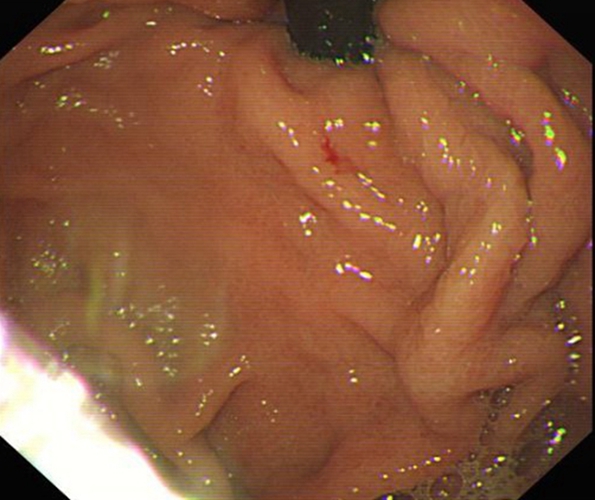

急性胃炎

急性胃炎圖片

急性胃炎陽性表現

急性胃炎陽性的表現

急性胃炎症狀表現

急性胃炎症狀的表現